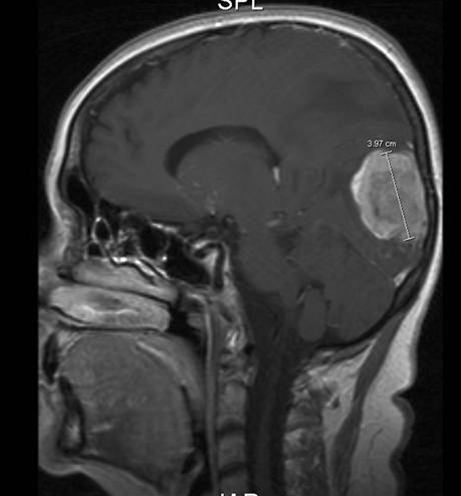

Hjerne, Metastase, MR-scanning

MR-scanning med kontraststof viser en metastase fra en kræftknude i brystet. Man ser den både axialt og saggitalt.

Gengivet med tilladelse fra Radiologisk afdeling, Universitetssygehuset Nord-Norge